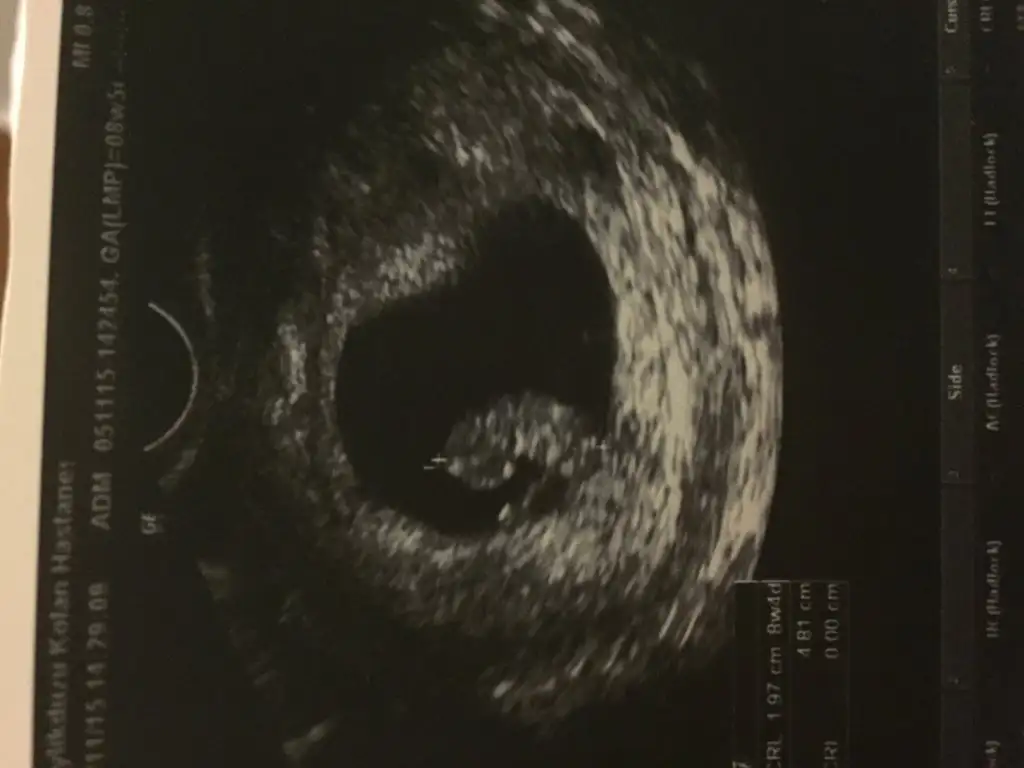

Kızlar varsa 7, 8, 9 haftalık ultrason görüntülerini atar mısınız..:cool:

canım ben yüklemiştim bunu tekrar yüklüyorum senin için 8+4 günlüktü

8+4.webp